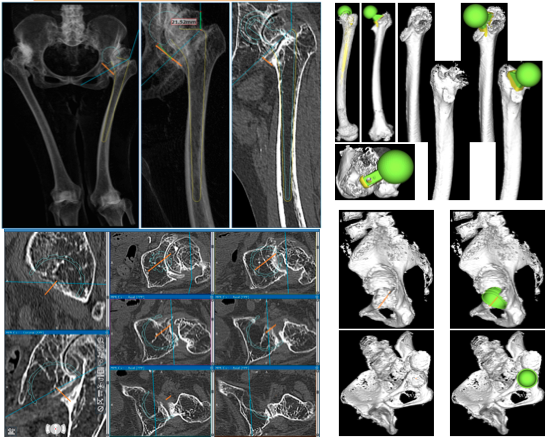

当院では、AMISで行う症例では原則、3Dテンプレートによる3次元での術前計画を行っています。

さらに、術前のCT画像をもとに、個々の患者さんごとに3Dプリンターで作成したオーダーメイドの実物大の骨モデル・患者適合型ガイドを作成して手術に臨むことで、より正確で安全な手術を心がけています。

3次元で術前計画を行うことで、個々の患者さんの骨の形状に合わせて、最適なインプラントを、理想的な位置に設置することが可能となります。

3Dテンプレートでは、インプラントを設置した状態で関節の動きのシミュレーションを行うことができるため、脱臼の原因となるインピンジメント(インプラントと骨が衝突して脱臼の原因となる)も予想して避けることが可能です。

3Dテンプレートにより、3次元で評価することができるため、より適切な機種、設置位置などを再現することが可能です。

骨モデルで実際の人工関節の設置角度や骨欠損の状態をより正確に把握することができます。